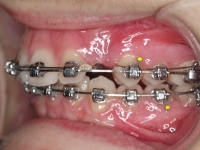

Clase II paciente 15 años

La paciente O.O. acude a nuestra consulta por:

– Canino 13 e incisivo lateral 42 en posición ectópica.

– Canino 23 incluido.

Con lo que decide realizarse un tratamiento de ortodoncia de duración de 24 meses con brackets damon Q.